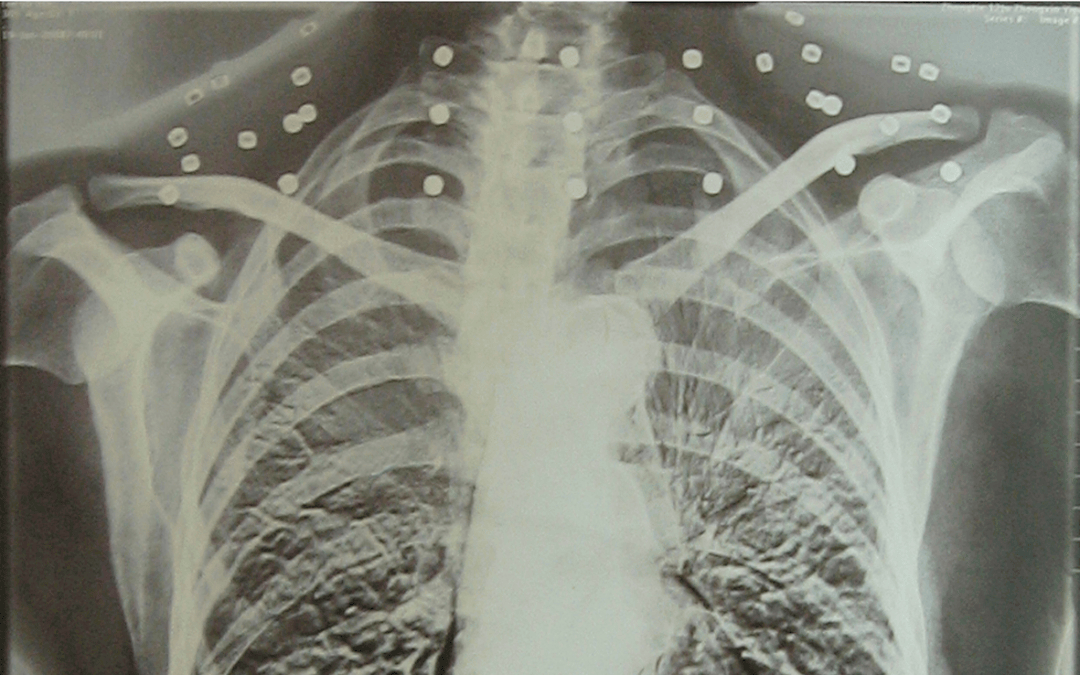

这张照片

是今年82岁的吴以先老人

拍摄的一张CT照

但实际上是

吴以先的颈部和腹部

共分布着33枚弹片

但是打进身体里的弹片

一直留在了体内

他体内的弹片都没有取出

这是他与战友并肩作战的见证

是他的勋章

与吴以先身上那33枚弹片

一起永远烙印在他心中